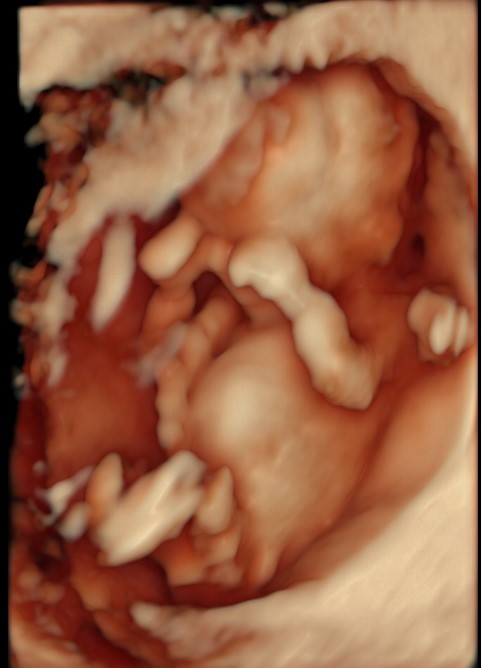

12+3 rasedusenädal (21.07.23) oli OSCARi UH, mille UH ma taas põdesin, et kas ikka loode on püsima jäänud. UH läks õnneks hästi ja Tessa oli ilusti kasvanud ja südametöö oli korras. Tessa istus mõnusalt oma pesas, kätud näo ees ja nabanöör üle parema õla nagu pildil näha. Plantsenta asetus oli tagaseinal ja seetõttu see nabanöör üle õla tal oligi, sest ta ise istus nägu mu kõhu suunas.